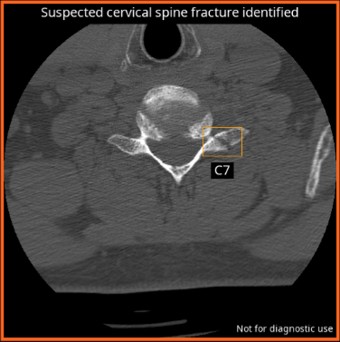

CINA-CSpine

CINA Trauma assists radiologists and trauma teams to detect critical injuries faster, prioritize life-saving interventions, and improve patient outcomes. This powerful solution integrates two AI tools—CINA-ICH and CINA-CSpine—working in tandem to identify two of the most urgent trauma-related conditions.

The bundle offers automatic detection of intracranial hemorrhages (ICH) and cervical spine fracture (CSpine) on Non Contrast CT(NCCT).